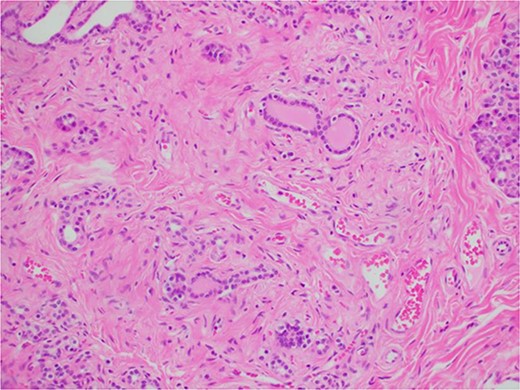

During a thorough inspection of the small bowel in its entirety, a yellow, lobulated oblong lump on the serosa of proximal jejunum was found (Fig. 1). A segment of small bowel including the lesion was resected and sent for histology. The small bowel was re-joined with a stapled anastomosis. Histopathological examination of the lesion revealed a 16 × 13 mm white, serosal nodularity (Fig. 1a). The underlying jejunal mucosa was normal (Fig. 2a). Histological sections were consistent with ectopic pancreatic tissue; they exhibited numerous acinar type glands associated with occasional islet of Langerhans, centred around a main pancreatic duct (Fig. 3). Some of the acinar units show gland drop out, fibrosis, atrophy, and scattered chronic inflammation, indicative of past and chronic pancreatitis (Fig. 4). Microscopically, the EP involved the submucosa and was abutting the serosa. No malignancy was present.

Microscopic histological images, showing (a) pancreatic acini and the exocrine pancreas within the ectopic pancreas. (b) The main pancreatic duct of the ectopic pancreas. (c) Islet’s of Langerhans (*) and the endocrine pancreas within the ectopic pancreas.